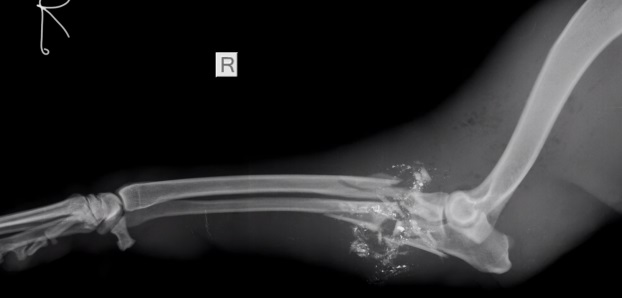

Resultó que la perra cerró con su cuerpo a los pequeños. La bala destrozó la pata delantera de Myra, pero los niños se salvaron. El asesino, al ver que se quedó sin balas, se retiró.

Perrita heroica, aunque muy maltratada, afortunadamente sobrevivió. Fue llevada a la clínica de la Sociedad de Protección y Cuidado de Animales de la Ciudad del Cabo (The Cape of Good Hope SPCA). Los veterinarios tuvieron que amputarle la pata delantera, pero Myra sobrevivió.